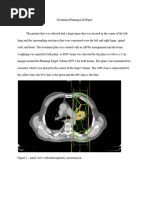

These differences can be further visualized on the DVH, above. The mean dose for the tumor in

the plan with inhomogeneity correction is 98.5% - a few percent less than the plan without any

correction. The minimum dose the tumor receives in the respective plans is 89%, compared to

94.4%. These can be better seen on the comparative DVH, below. The difference in tumor

coverage is evident. The plan without any correction (triangles) has visibly better tumor coverage

overall. However, due to the effect of density inhomogeneity, as discussed earlier, this is not an

accurate representation of the dose deposition that is actually occurring. Relying on information

from a plan that hasn’t had any inhomogeneity correction applied, leads to overestimation of

tumor coverage, and therefore tumor control.

The above comparative DVH also demonstrates that the plan without correction overestimates

the amount of dose deposition within the ipsilateral lung – the blue line. The effect of higher

density material in bone is shown in the dose reported to the spinal cord – the red line. This

reflects the bowing in of the isodose lines, as seen on the medial edge of the beam in the plan

that had a correction applied.